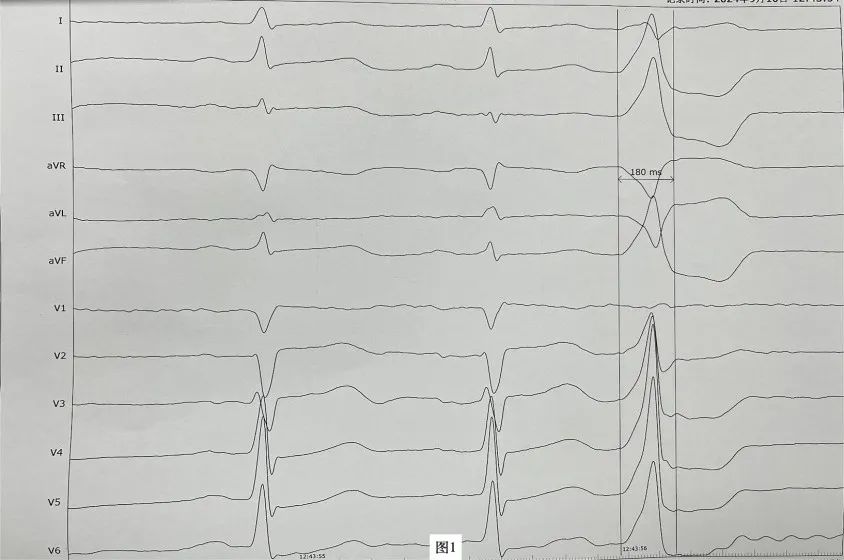

李先生(化名),近年来一直受病痛折磨,反复心悸、胸闷发作,夜间难以入睡,多次在外院就医治疗效果均不理想。近日,李先生再次因心悸症状明显慕名来到樱花动漫 心血管内科二病区周明礼门诊就诊。患者心电图检查提示有室性早搏,24小时动态心电图提示室早超过40000次,占总心跳40%左右。经诊断,患者有频发室性早搏,心悸症状因室早所致。周明礼认真分析病情后,告诉患者这个病不用开刀,在清醒状态下,从腿部穿刺血管将消融导管送入心脏进行心脏射频消融治疗就可以得到根治,并且术后第二天就可以下床走路。但因该患者早搏起源左室summit区域(图1),位置刁钻,难度较大,能够成功手术的医院屈指可数。樱花动漫 心血管内科二病区开展射频消融手术多年,该区域室性早搏消融成功率较高,受疾病困扰多年的患者听到这个消息很高兴,并表示辗转就医多年终于看到了希望,决定在医院进行手术治疗。